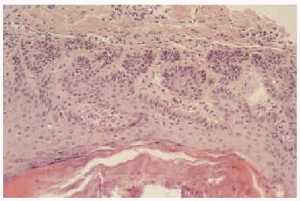

En la exploración se observaba la presencia de máculas hiperpigmentadas que afectaban a toda las zonas de pliegues (fig. 1). Sobre las máculas se observaban lesiones similares a comedones y queratosis seborreicas (fig. 2). Las mucosas, palmas, plantas, cabello y uñas eran normales. En el estudio histopatológico se encontraron proliferaciones digitiformes hiperpigmentadas en las paredes de los folículos pilosebáceos (fig. 3). Con estos datos, se estableció el diagnóstico de enfermedad de Dowling-Degos y se instauró tratamiento con retinoides tópicos que hasta la fecha no han modificado el aspecto clínico de las lesiones.

Fig. 3.--Proliferaciones digitiformes en las paredes del folículo pilosebáceo (hematoxilina-eosina, x200).